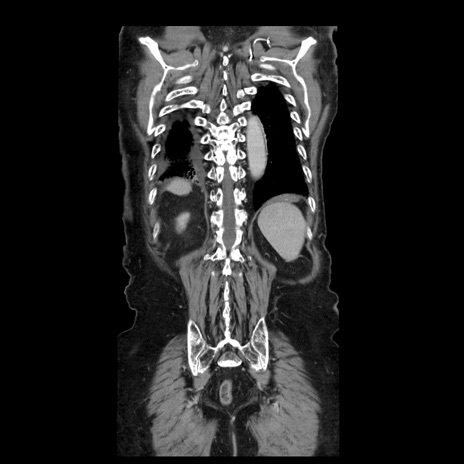

横断像